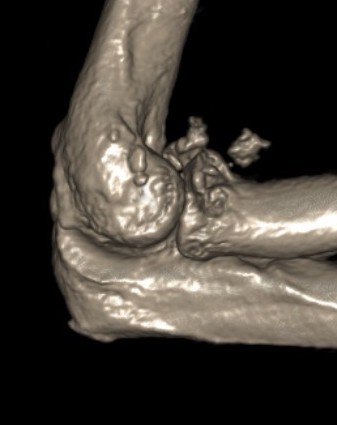

Elbow dislocation with radial head fracture

Management

Critical to elbow stability

Based upon Mason classfication

Terrible Triad

Definition

Elbow dislocation with radial head fracture + coronoid fracture + MCL tear